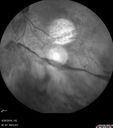

PDR NVD left eye and NVE right eye555 views41 year old diabetic woman with PDR in both eyes. High risk in the left eye. She had PRP, Avastin, and vitrectomy x 2 in the left eye with final vision of 20/25. The right eye had eventually PRP laserApr 07, 2017

PDR NVD left eye and NVE right eye397 views41 year old diabetic woman with PDR in both eyes. High risk in the left eye. She had PRP, Avastin, and vitrectomy x 2 in the left eye with final vision of 20/25. The right eye had eventually PRP laserApr 07, 2017

PDR NVD left eye and NVE right eye388 views41 year old diabetic woman with PDR in both eyes. High risk in the left eye. She had PRP, Avastin, and vitrectomy x 2 in the left eye with final vision of 20/25. The right eye had eventually PRP laserApr 07, 2017